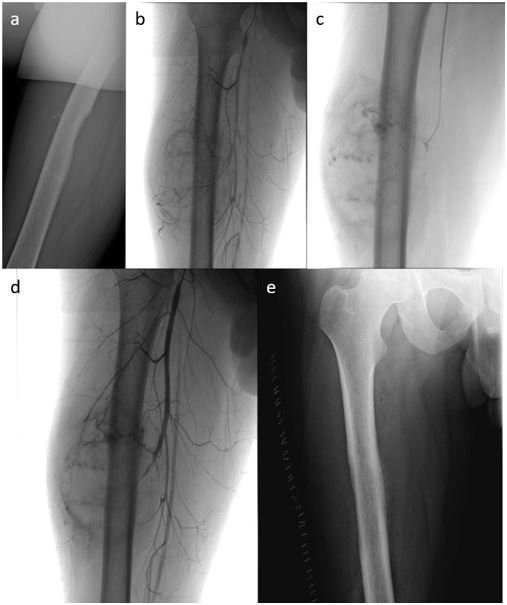

Considering the massive vascularization demonstrate in the MRI scan we performed a preoperative trans-arterial embolization of the lesion in order to reduce the blood loss during surgery (Figure 2).

The angiography showed a massive vascularity of the lesion with arterial feeders from branches of the right deep femoral artery. Then the catheter was brought up to the right deep femoral artery and arteriography confirmed the lesion vascularity. A microcatheter and a microwire were used to navigate the major arterial feeders then an embolization using a microsphere of 400 um was performed.

Completion arteriography demonstrate stop of flow with correct embolization of the lesion without embolization of no-target tissue (Figure 3).

Figure 3a-3e: 3a shows pre-operative radiograph, then 3b-3d are intraoperative radiograph demonstrating respectively pre-embolization angiography, embolization with microspheres and completion angiography that shows complete embolization of the lesion. 3e shows post-surgery radiograph.

At surgery, lateral side of the thigh approach was done, the lesion was dissected from quadricep muscle and removed from the cortex. Deep cortex curettage and phenol/alcohol instillation was performed as an adjuvant reducing risk of recurrences. Postoperative complications were not noticed and the transcatheter embolization was efficacy reducing the intraoperative bleeding.

At the histological analysis cortical erosion was confirmed but no involvement of medulla was observed. Two days after surgical resection the patient underwent to an internal fixation with carbon intramedullary nail in order to prevent pathological fracture.